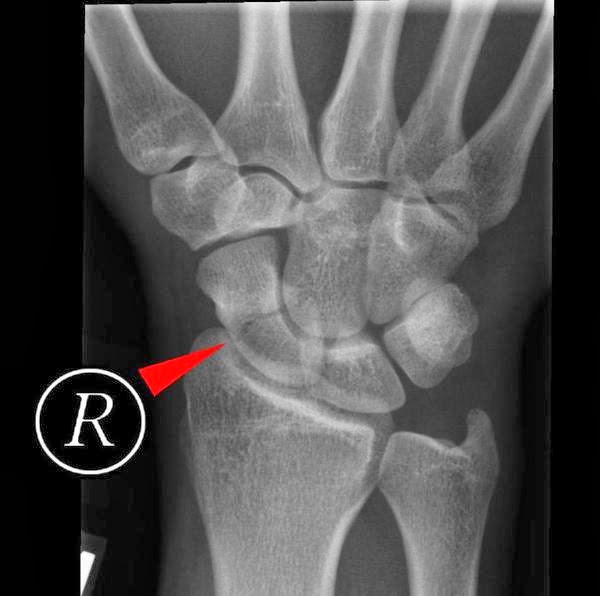

From resus.com.au

From www.researchgate.net

Radiograph of the left wrist shows stress fracture of the left scaphoid How Do You Know If You Fractured Your Scaphoid Can also occur from axial loading to wrist or direct blow to the scaphoid. Scaphoid divided into tubercle, distal pole, waist (most common fracture site. What you need to know about a broken wrist. Scaphoid fractures are almost always caused. The scaphoid bone is one of the eight smaller carpal bones. Your scaphoid is one of your carpal bones, the. How Do You Know If You Fractured Your Scaphoid.